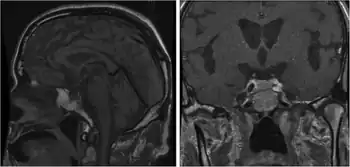

Adrenocorticotropic hormone deficiency is a result of a decreased or absent production of adrenocorticotropic hormone (ACTH) by the pituitary gland.[1] It can be associated with TBX19.[2]